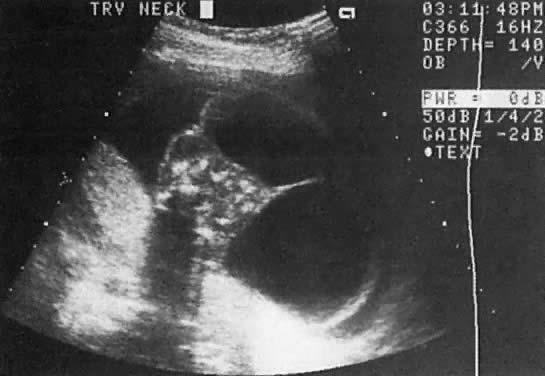

In this disorder, poor development of communication channels between the jugular veins and the cervical lymph sacs (jugular lymphatic obstruction sequence) results in the formation of cystic hygromas (Fig. 29). These can vary in size depending on the degree of obstruction. In some cases, cystic hygromas have been noted to regress in utero, implying growth in the communication channels with advancing gestational age.83 In mild cases, the differential diagnosis includes thickening of the nuchal occipital fold secondary to aneuploidy.84 In severe cases, massive fetal hydrops develops and intrauterine fetal death occurs in the second trimester of pregnancy.

Fig. 29. Cross-section of fetal neck, showing very large cystic hygromas extending toward the right side of the echogram.